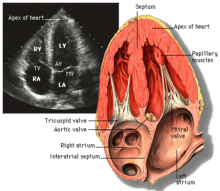

| Each figure contains a TTE with a black background, and a corresponding colored illustration. | Patrick J. Lynch and C. Carl Jaffe, Yale University, 2006. | ||||||||||

| Click on a figure to enlarge it and see some parts of the heart identified. RV, right ventricle; LV, left ventricle; RA, right atrium; LA, left atrium; TV, tricuspid valve; MV, mitral valve; AV, aortic valve; RVOT, right ventricular outflow tract; LVOT, left ventricular outflow tract | |||||||||||